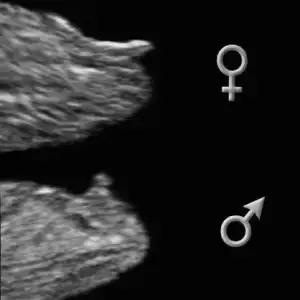

Benimkinide yorumlarmısınız...11+6 yız. Eki Görüntüle 1162041

Masallah cnm erkek bnce çikintı dik bide bas popo uzunluk oranı erkek fikrine kapılmma ndn oldu

erkek erkek kesin...

Cnm o gozuken bacak deilse erkek sanırım kaç haftlıktı doktor bişe demedimi

Dr kesinlikle kiz dedi

evt bu resim icin erkek dedim cnm bnmm yukari bakio nub ucu

Buda benim bebisimn rsmi szce ne? Ben anlamiorm nub dan